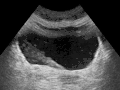

Several forms of medical imaging are used to view the ureters and urinary tract.[22] Ultrasound may be able to show evidence of blockage because of hydronephrosis of the kidneys and renal pelvis.[22] CT scans, including ones where contrast media is injected intravenously to better show the ureters, and with contrast to better show lesions, and to differentiate benign from malignant lesions.[22] Dye may also be injected directly into the ureters or renal tract; an antegrade pyelogram is when contrast is injected directly into the renal pelvis, and a retrograde pyelogram is where dye is injected into the urinary tract via a catheter, and flows backwards into the ureters.[22] More invasive forms of imaging include ureteroscopy, which is the insertion of a flexible endoscope into the urinary tract to view the ureters.[23] Ureteroscopy is most commonly used for medium to large-sized stones when less invasive methods of removal cannot be used.[23]